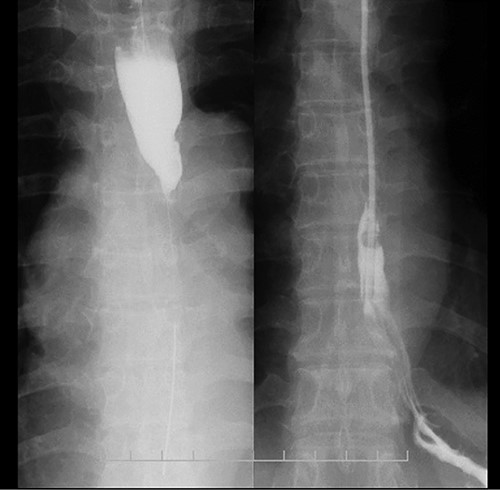

Esophagram findings; the esophagram shows stricture in the middle thoracic esophagus; a nasogastric tube could pass through the stenosis, and tube feeding was started.

A 48-year-old woman accidentally ingested an alkaline detergent and was transported to the emergency medical care center of a local hospital. Conservative treatment using a proton pump inhibitor and a mucosal protectant was initiated. Although this treatment was lifesaving, an esophageal stricture developed, and the patient developed dysphagia and gradually lost weight. Two months later, she was referred to our hospital for balloon dilatation. The esophageal stenosis was severe and >10 cm in length (Fig. 1); therefore, balloon dilatation was impossible. A nasogastric tube was inserted to improve the patient’s nutritional status. After 3 months, her nutritional status improved, and surgical treatment was deemed necessary.